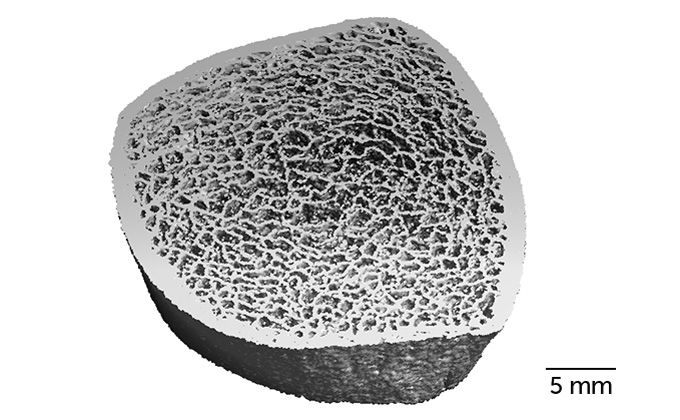

Gabel was part of a team that tracked 17 astronauts. Each of these 14 men and three women had spent from four to seven months in space. The team used a type of computed tomography to measure the 3-D structure of bone on a fine scale. They focused on the structure of the tibia (in the lower leg) and radius bone (in the lower arm). This imaging revealed details on a scale of 61 micrometers. That’s finer than the thickness of a human hair.

The researchers took images of the bones four times — before spaceflight, then when the astronauts returned home from space, and again six months and one year later. From these pictures, Gabel’s team calculated an astronaut’s bone strength and density at each of those times.

Increasing weight-lifting exercises in space could help alleviate bone loss in the legs, says Steven Boyd. He’s also a Calgary exercise scientist. “A whole bunch of struts and beams all held together give your bone its overall strength,” says Boyd. “Those struts or beams are what we lose in spaceflight.” Once these microstructures (called trabeculae) are lost, you can’t rebuild them, he says. You can, however, strengthen the remaining ones. And upon return to Earth’s gravity, the remaining micro-structures did thicken, Gabel’s team found.